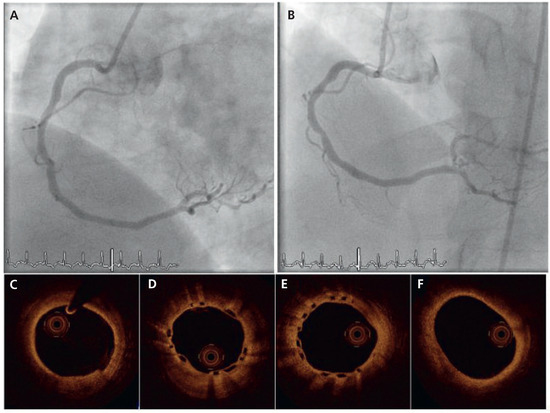

A 51-year-old male was referred for coronary angiography. His known cardiovascular risk factors were insulin-dependent diabetes mellitus, dyslipidaemia, arterial hypertension, obesity (BMI 33 kg/m2) and a family history of coronary artery disease. Coronary angiography (Figure 1) showed patent left main (LM), left anterior descending artery (LAD) and circumflex artery (LCx) without obstructive disease. A second obtuse marginal branch (OM2) and the distal right coronary artery (RCA) demonstrated high-grade stenoses. After angioplasty of OM2 with subsequent implantation of one 2.25 × 12 mm-everolimus-eluting stent, (XIENCE V, Abbott Vascular, Santa Clara, CA), at 16 atm, the stenosis in the RCA was treated with a bio-resorbable everolimus-eluting coronary scaffold. Briefly, a 6F Judkins right 4 guiding catheter was positioned at the RCA ostium. A 0.014’’ guidewire (BMW, Abbott Vascular, Santa Clara, CA) was advanced into the posterolateral branch and the lesion was treated by single balloon inflation (3.0 × 12 mm-Apex, Boston Scientific, Nantik, MA), at 12 atm, which was followed by the implantation of one 3.0 × 18 mm-everolimus-eluting bioresorbable vascular scaffold, (BVS, Abbott Vascular, Santa Clara, CA), at 12 atm. The control angiography, the intravascular ultrasound and the optical coherence tomography showed satisfactory results. The recovery was uneventful and the patient was discharged on the following day. A lifelong prescription of aspirin (100 mg daily) was prescribed, and clopidogrel (75 mg daily) was prescribed for 12 months. At 6-month follow-up (Figure 2), control angiography was performed and demonstrated a smooth artery without visual angiographic late loss. Both an intravascular ultrasound study and optical coherence tomography revealed neoendothelialisation of the scaffold struts without significant vessel shrinkage or excessive neointimal hyperplasia. Clinical follow-up to 12 months was uncomplicated.

Figure 1.

Angiographic and optical coherence tomography (OCT) findings during index procedure. (A) Dye injection in the right coronary artery (RCA) demonstrated one 10 mm-stenosis of the distal part (*). (B) BVS scaffold platform is radiolucent but two small platinum markers allow accurate placement of the device. (C) Final angiogram after scaffold implantation. (D–G). Cross-sectional OCT imaging from distal to proximal: the BVS struts (S) are discernible with sites showing sharply defined, bright reflection borders, usually described as having a “box-shaped” appearance (arrows). One strut was not apposed to the vessel wall (*). (H) Longitudinal reconstruction.